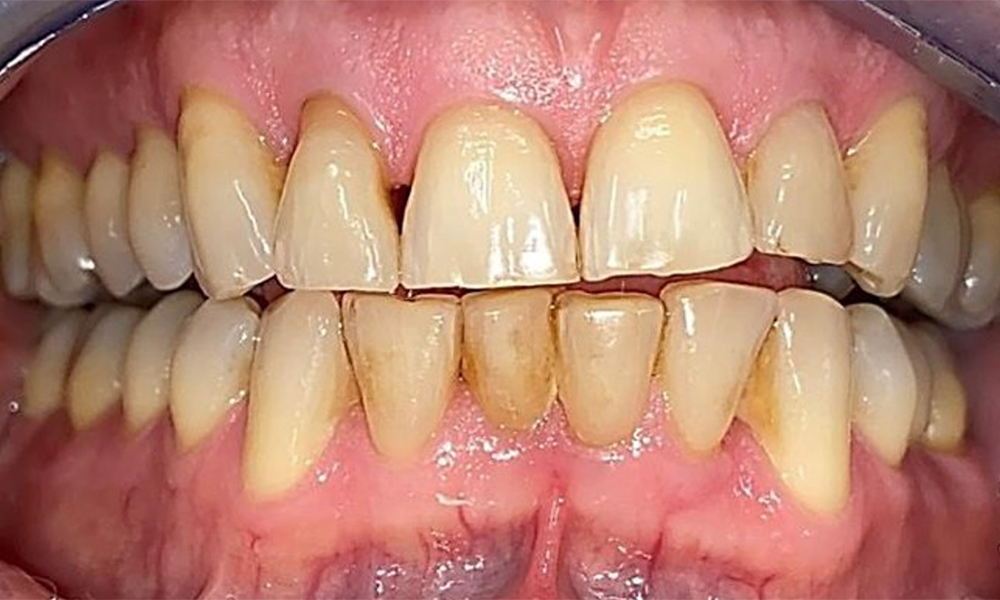

Frontal view with loss of the interdental papillae between 12 and 11.

Fig. 2 Frontal view with loss of the interdental papillae between 12 and 11. © Dr R. Krapf

Right lateral view. Loss of the interdental papillae.

Fig. 3 Right lateral view. Loss of the interdental papillae. © Dr R. Krapf

The patient has a full dentition with 28 teeth, which includes amalgam and composite fillings in the molar and premolar regions. There is a visible clinical marginal gap present on tooth 14. Tooth 27 has an adequate gold inlay. There are also generalized attritions and abrasions. (Fig. 2, Fig. 3, Fig. 4, Fig. 5, Fig. 6)

Periodontal findings

The patient has stage II, grade B periodontitis (5). At 1 to 3 mm, the clinical probing depths were within the physiological range. Localized probing depths of 5 mm were observed on the mesiopalatal aspects on both 17 and 27. There are generalized recessions of 1–3 mm with partial loss of the interdental papillae (Fig. 2, Fig. 3, Fig. 4)